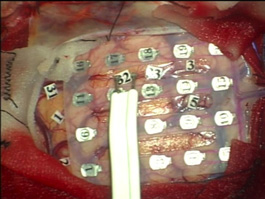

大脳マッピング Brain Mapping

脳の機能を微弱な電気刺激で調べます。運動機能を調べる場合は全身麻酔で手術を行うことが出来ます。

大脳皮質マッピング Cerebral cortex Mapping

大脳の表面の神経細胞の機能を調べます。運動野と呼ばれる体の動きを司る脳を見つけ出し、その部分を損傷しないように注意しながら手術を行います。

皮質下マッピング Subcortical Mapping

大脳皮質の神経細胞の情報は脳内の神経線維を通って脳の他の場所に運ばれたり、脊髄を通って全身の臓器とのやり取りをしています。

脳腫瘍を摘出する際に微弱な電気刺激でこれらの大切な神経線維を確認し、それを傷つけないようにします。当院では独自開発の電極により従来の方法よりさらに安全な神経機能マッピングと摘出術を実現しました。

(左図)皮質下マッピング用電極 (NY Tract Finder)

(右図)NY Tract Finderによる神経線維刺激

(図)正確な脳マッピングにより機能を守り、最大限の腫瘍摘出を行います。